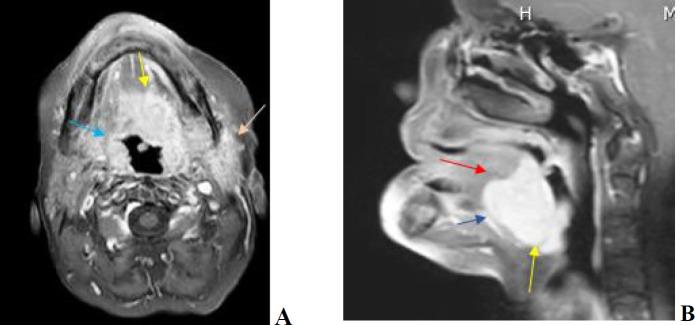

Sclerosing microcystic adenocarcinoma (SMA) is an uncommon neoplasm of the oral cavity, with only 14 reported cases documented in the literature. We present a case of SMA in a 65-year-old woman with a history of high-grade lymphoma who developed clear cell changes in the deep muscular layer of the tongue. Currently, the diagnosis of SMA relies on careful morphological evaluation and the exclusion of other potential differential diagnoses.

硬化性微囊性腺癌(SMA)是一种罕见的口腔肿瘤,文献中仅记载了14例报告病例。我们报告一例65岁女性的SMA病例,该患者有高级别淋巴瘤病史,其舌深层肌肉层出现了透明细胞改变。目前,SMA的诊断依赖于仔细的形态学评估以及排除其他潜在的鉴别诊断。

Magnetic resonance imaging findings of sclerosing microcystic adenocarcinoma: A case report and review of the literature.硬化性微囊性腺癌的磁共振成像表现:一例报告并文献复习

Radiol Case Rep. 2023 Aug 3;18(10):3626-3631. doi: 10.1016/j.radcr.2023.07.050. eCollection 2023 Oct.